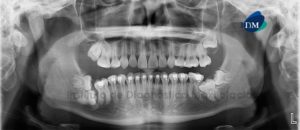

Paciente de sexo femenino de 32 años de edad acude al Instituto de Diagnóstico Maxilofacial para evaluación general de ambos maxilares. A la evaluación panorámica